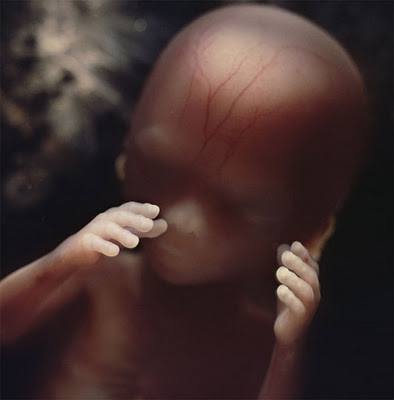

Բարակ մաշկի տակից երևացող արյունատար անոթները:

18-րդ շաբաթ, մոտ 14 սմ երկարություն: Պտուղն արդեն ընդունակ է ընկալել արտաքին աշխարհից եկող ձայները: